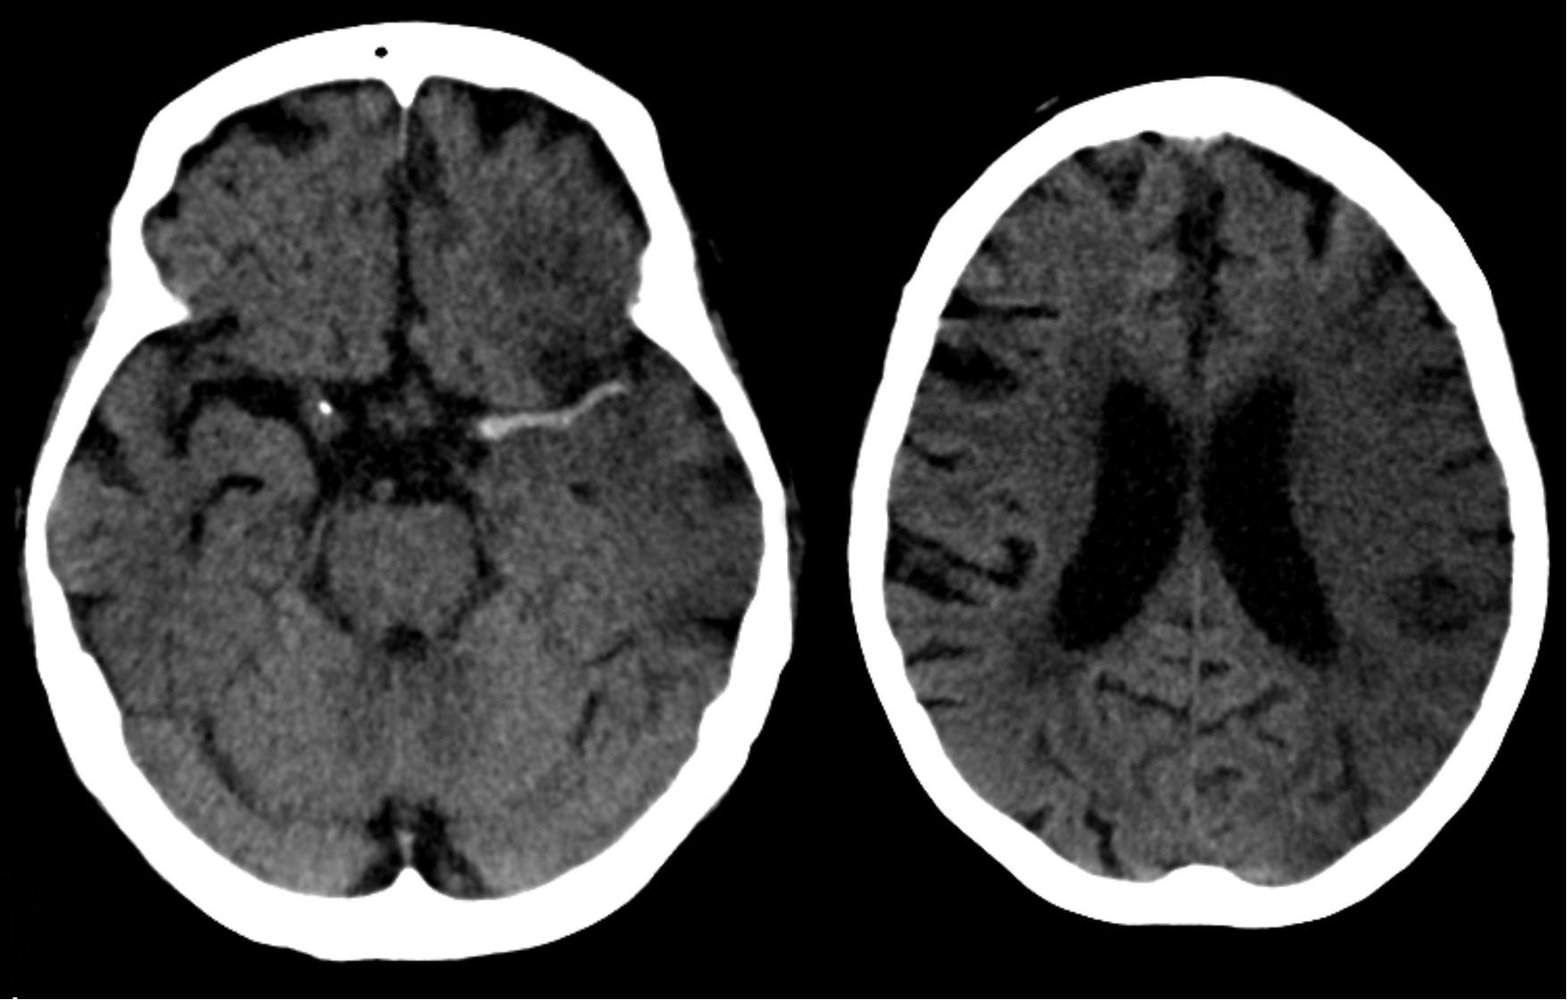

- An abnormal neurological status may be caused by:

Primary brain injury (e.g., stroke, TBI, status epilepticus)

- Systemic conditions (with or without secondary brain injury): see “Causes of AMS and coma.”

- Consider immediate neurology and/or neurosurgery consult for suspected acute stroke, intracranial bleed, or cerebral herniation.

Neuroimaging: e.g., CT head

Stroke (hemorrhagic or ischemic)